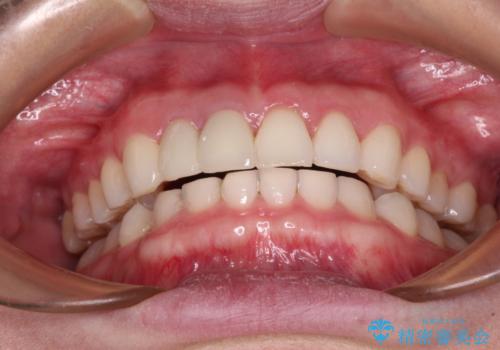

治療前、下顎前歯はほとんど見えない咬み合わせでしたが、矯正治療によりディープバイトが改善されました。

矯正治療中に前歯2本のクラウンは外れてしまい、途中仮歯に替える必要があったので期間は掛かりましたが、歯列も整い、負担のかからない咬み合わせを達成することができました。